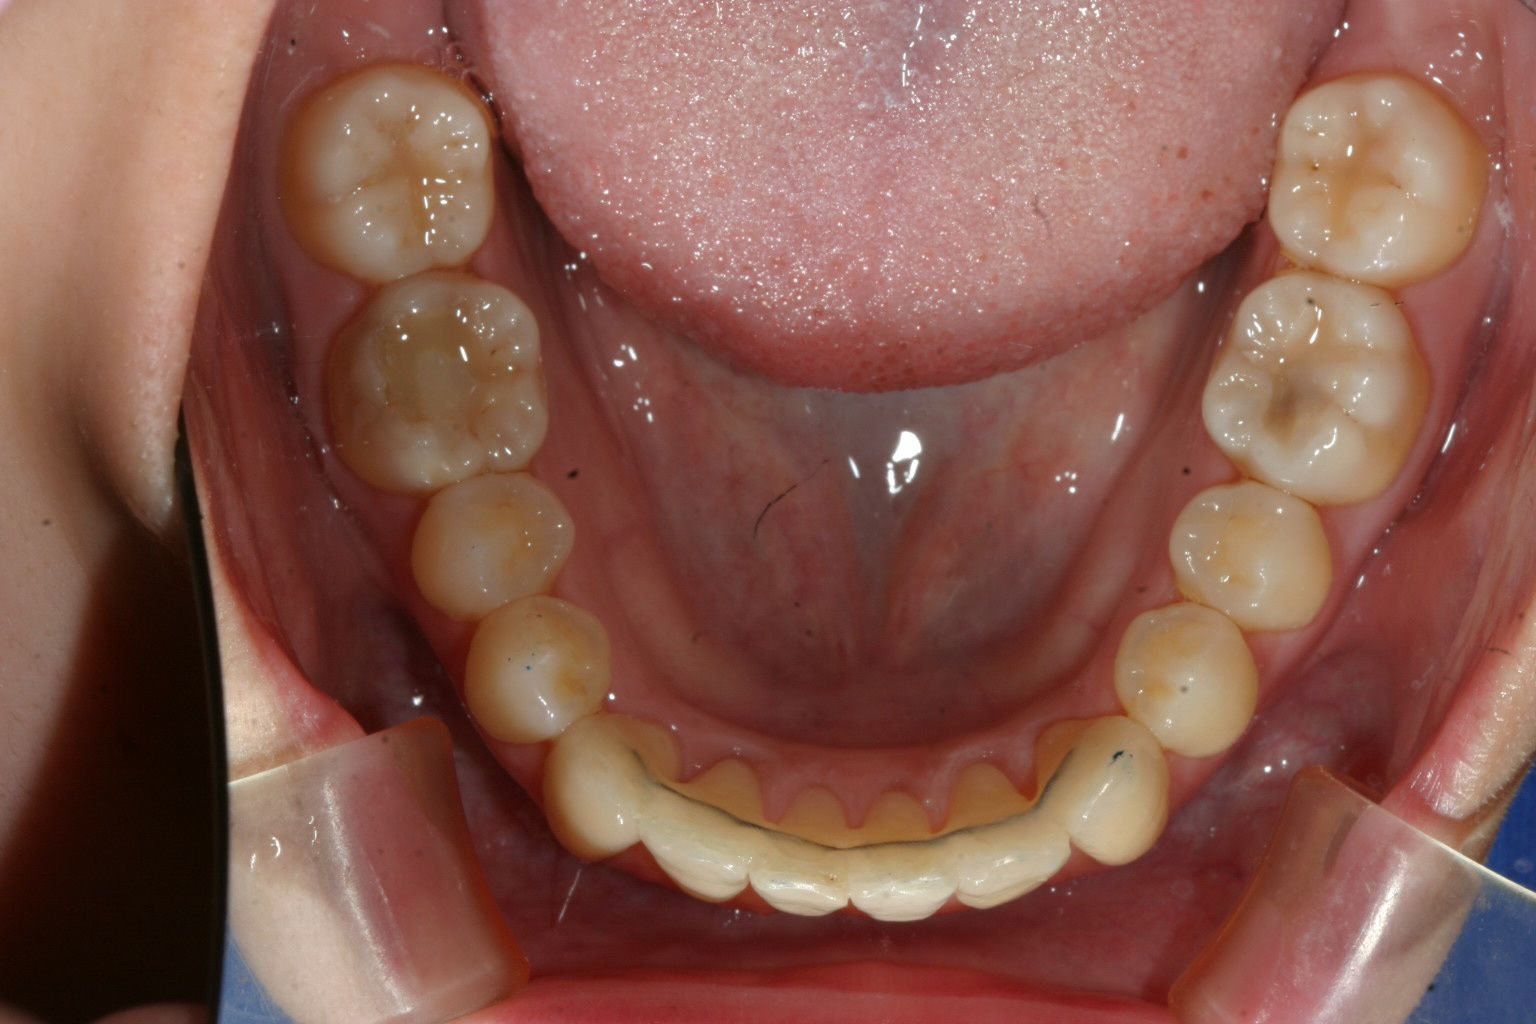

下の前歯は歯列がV字形の為4本の前歯が上手く並ばずガタガタになってます。

こちらも歯列をU字形にする事により綺麗に改善してます。

こちらの症例は典型的な症例で歯列形が悪い為の不正咬合です。

これって言って特別何をしたって事無く歯列を V字形をU字形にするだけでここまで改善します。

皆様の中にこの様な感じの歯列でお悩みの方が居られましたらどうぞ気楽に相談にお越しください。